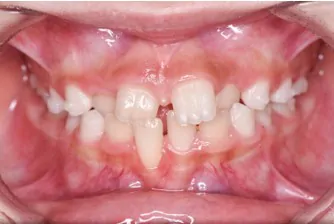

プレオルソの症例

Before

After

症例の概要

この患者さんは10歳の男の子で、前歯が出ている事を主訴に来院されました。

日中の1時間と就寝時に装着していただいて、舌の位置や飲み込みの指導を約6ヶ月使用した初診時と術後です。

比較をすると主訴の右上の前歯が内側に入ってきて、噛み合わせが深かった(噛んだ時に下の前歯があまり見えていない状態)のが浅くなり、

上の歯並びのアーチが狭かったのが、広がって綺麗に歯が並んできていることがわかります。

この様に状態によってはワイヤーを装着せずに、改善させることができます。